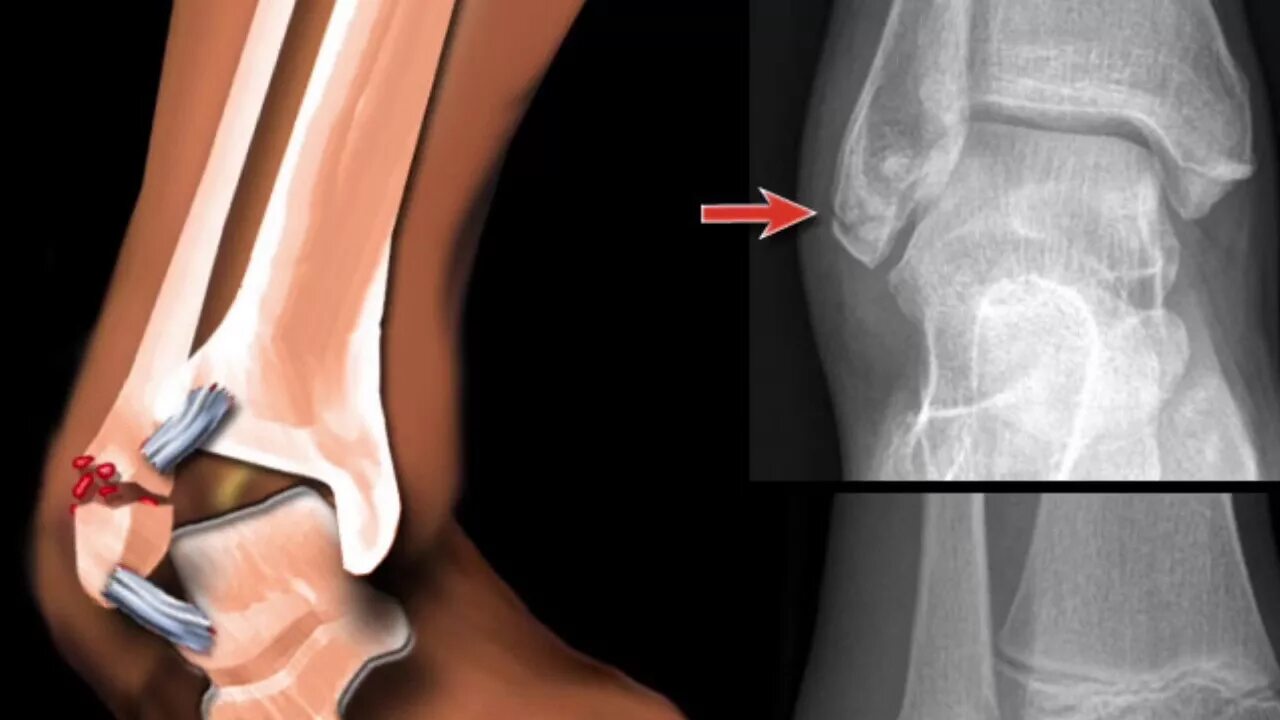

Трещина в кости ноги сколько